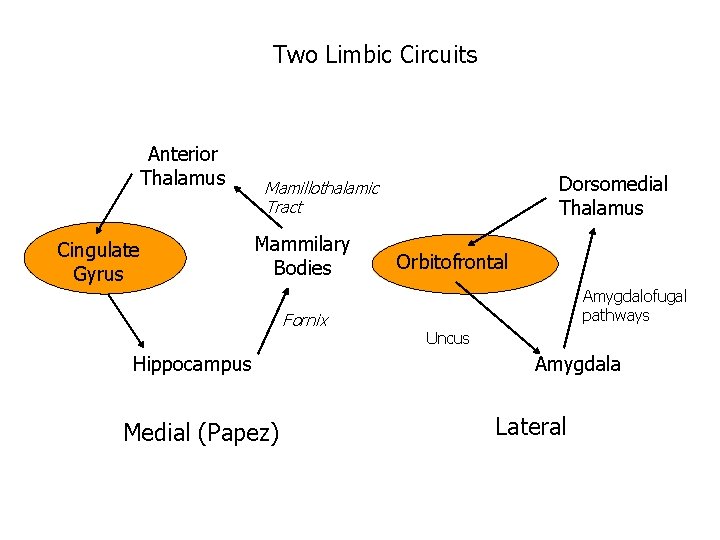

Two Limbic Circuits Anterior Thalamus Cingulate Gyrus Dorsomedial Thalamus Mamillothalamic Tract Mammilary Bodies Fornix Hippocampus Medial (Papez) Orbitofrontal Amygdalofugal pathways Uncus Amygdala Lateral

Two Limbic Circuits and the Two-system theory of amnesia Anterior Thalamus Cingulate Gyrus Dorsomedial Thalamus Mamillothalamic Tract Mammilary Bodies Orbitofrontal Amygdalofugal pathways Fornix Uncus Hippocampus Amygdala PRPH Medial (Papez) Lateral

Two Limbic Circuits and the Two-system theory of amnesia Anterior Thalamus Cingulate Gyrus Dorsomedial Thalamus Mamillothalamic Tract Mammilary Bodies Fornix Hippocampus Medial (Papez) Orbitofrontal Amygdalofugal pathways Uncus Amygdala Lateral

Two Limbic Circuits Anterior Thalamus Cingulate Gyrus Dorsomedial Thalamus Mamillothalamic Tract Mammilary Bodies Fornix Hippocampus Medial (Papez) Orbitofrontal Amygdalofugal pathways Uncus Amygdala Lateral

Two Limbic Circuits Anterior Thalamus Cingulate Gyrus Dorsomedial Thalamus Mamillothalamic Tract Mammilary Bodies Fornix Hippocampus Medial (Papez) Orbitofrontal Amygdalofugal pathways Uncus Amygdala Lateral Bauer, Grande, & Valenstein, 2003